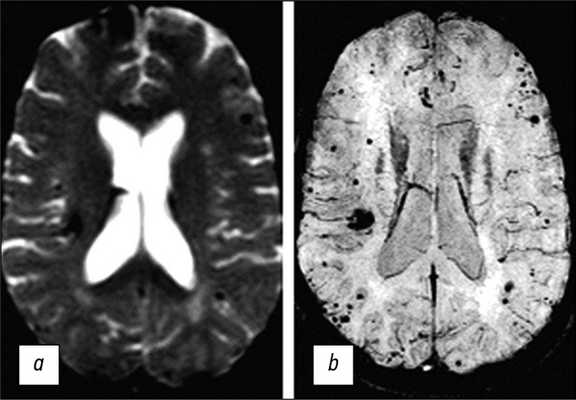

Отложения гемосидерина внутри и вокруг КМ, которые считаются типичным признаком повторных субклинических кровоизлияний или лизиса эритроцитов, обеспечивают магнитную восприимчивость этого патологического образования, особенно при высокой напряжённости магнитного поля. Неоднородность магнитного поля в присутствии гемосидерина также способствует дифференциации кровотока и эффектов гемосидерина в КМ (рис. 2) [16, 17].

![]()

Рис. 2. МР-томограммы головного мозга в аксиальной плоскости, выполненные в режимах Т1-ВИ (a,c), Т2-ВИ (b), T2*GRE (d), демонстрируют более детальную визуализацию структуры КМ (тот же случай, что и на рис. 1). На изображениях визуализируется очаговое образование характерной ячеистой структуры с гипоинтенсивным периферическим сигналом на Т2-ВИ. Последовательность T2*GRE подчеркивает «цветущий» эффект гемосидерина.

В целом следует отметить, что использование последовательностей T2*GRE даёт возможность выявить «цветущий» эффект гемосидерина и повысить чувствительность обнаружения КМ. Применение последовательностей SWI, особенно при использовании уровня магнитного поля 3 Тл, позволяет выявлять многоочаговые поражения в случае семейных КМ, которые не могут быть установлены при использовании изображений T2*GRE (рис. 4) [27]. Применение таких подходов значительно повышает диагностические возможности МРТ.

Рис. 4. МР-томограммы головного мозга в аксиальной плоскости, выполненные в режимах T2*GRE (a) и SWI (b). Изображения в режиме SWI позволяют выявить дополнительные очаги КМ, не визуализируемые в режиме T2*GRE.